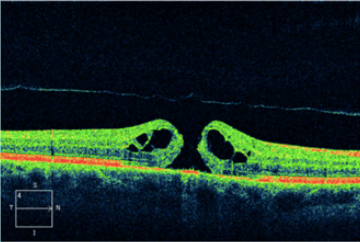

Cirurgias Retina

- Vitrectomia posterior: descolamento de retina, buraco macular e membrana epirretiniana

- Injeção Intraocular: edema macular, DMRI, oclusões vasculares.